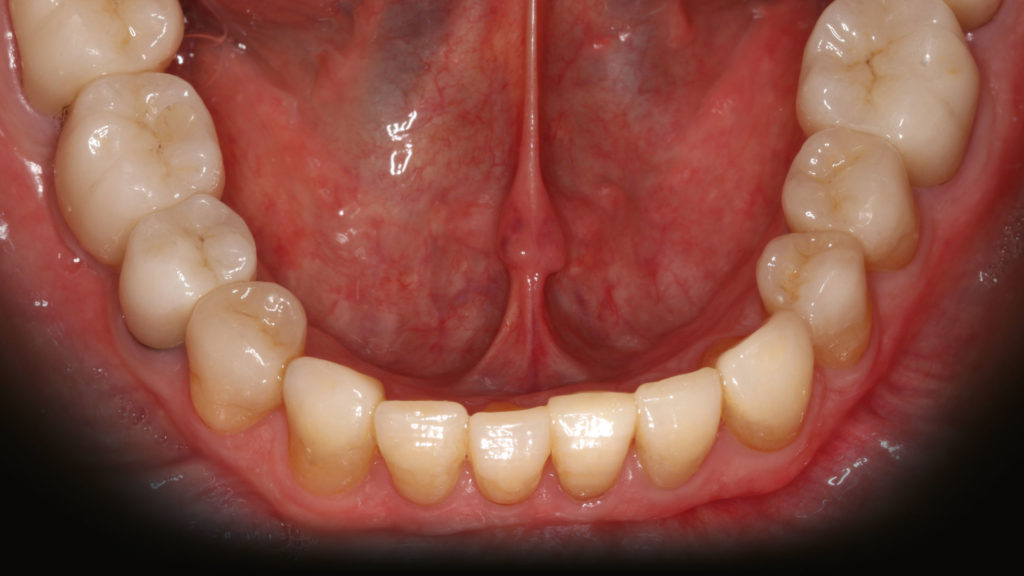

Im Labor konnten die vollkeramischen Restaurationen in der Presstechnik hergestellt werden (Abb. 8 bis 11). Die exakte Bisshöhe wurde zuvor im Mund evaluiert. Herstellung und Eingliederung der Veneers gestalteten sich dank des Wellenschliffs deutlich einfacher als mit anderen Veneer-Präparationsarten, da die Restaurationen am Zahn eine definierte Position hatten. Die adhäsive Eingliederung folgte den bekannten Abläufen. Die keramischen Restaurationen wurden geätzt beziehungsweise für das Verkleben konditioniert (Abb. 12). Nach dem Reinigen der Zähne wurden die Oberflächen mit Phosphorsäuregel vorbereitet, abgespült und getrocknet, mit Primer vorbehandelt, und es wurde Haftvermittler beziehungsweise Bonder aufgetragen (Abb. 13 bis 17). Nach dem Applizieren des Befestigungsmaterials konnten die Restaurationen eingegliedert und Materialüberschüsse entfernt werden (Abb. 18 und 19). Nach der Lichthärtung wurden die Ränder geglättet und die approximalen Kontakte angepasst sowie final poliert (Abb. 20 bis 24). Dabei zeigte sich ein weiterer Vorteil des Pfullinger Wellenschliffs. Der Übergang zwischen Zahn und Keramik ist dank des „diffusen“, bewusst unregelmäßig angelegten Präparationsdesigns optisch kaum wahrzunehmen. Eine Kontrolle der funktionellen Gegebenheiten bildete den Abschluss der prothetischen Therapie. Die in der Initialphase stabilisierte neue vertikale Bisshöhe konnte 1:1 mit den keramischen Restaurationen übernommen werden (Abb. 25).

Grundsätzlich ist es bei einer solchen Therapie unverzichtbar, während der prothetischen Phase die neue Bisshöhe zu erhalten. Daher wurde wie im ersten dargestellten Fall zunächst der Oberkiefer präpariert, mit Provisorien versorgt und im Unterkiefer die Schiene wieder eingegliedert. Nach der therapeutischen Phase wurden im Labor die vollkeramischen Restaurationen hergestellt. Während im vorangegangenen Fall indirekte temporäre Kompositrestaurationen („Deckel“) für die Unterkiefer-Frontzähne im Labor erstellt worden waren, kam in diesem Fall – aufgrund des vergleichsweise geringen Platzangebots – die direkte Methode zur Anwendung. Nach dem Einsetzen der vollkeramischen Restaurationen im Oberkiefer diente ein im Labor auf der Basis eines Wax-ups hergestellter Silikonschlüssel (transparentes Formteil) dem Herstellen temporärer Chairside-Restaurationen aus lichthärtendem Komposit. Der Patient testete in den folgenden Wochen die Situation und die neue Bisslage. Danach erfolgte die Präparation der Zähne im Unterkiefer. Die Zähne 46, 47, 35, 36 (Implantat), 37, 38 wurden für die Aufnahme von Kronen und 44/34 sowie 45 für Teilkronen (mit vestibulärem Wellenschliff) vorbereitet und die Frontzähne im Sinne eines optimalen Substanzerhalts nach dem „Pfullinger Wellenschliff“ präpariert (Abb. 27). Zahn 41 hatte bereits eine Krone, weshalb dort die Präparation nur leicht angepasst worden ist. Bei diesem Fall wurde ein reduzierter Wellenschliff vorgenommen. Das Herstellen der keramischen Restaurationen sowie die adhäsive Eingliederung folgten dem im Fall 1 beschriebenen Vorgehen (Abb. 28 bis 34). Erneut spielte der Wellenschliff seine Vorteile aus: vereinfachtes Handling in Praxis und Labor, geringe Invasivität sowie aufgrund des unregelmäßig verlaufenden Präparationsrands diffuser, augenscheinlich nicht sichtbarer Übergang zwischen Zahn und Keramik.